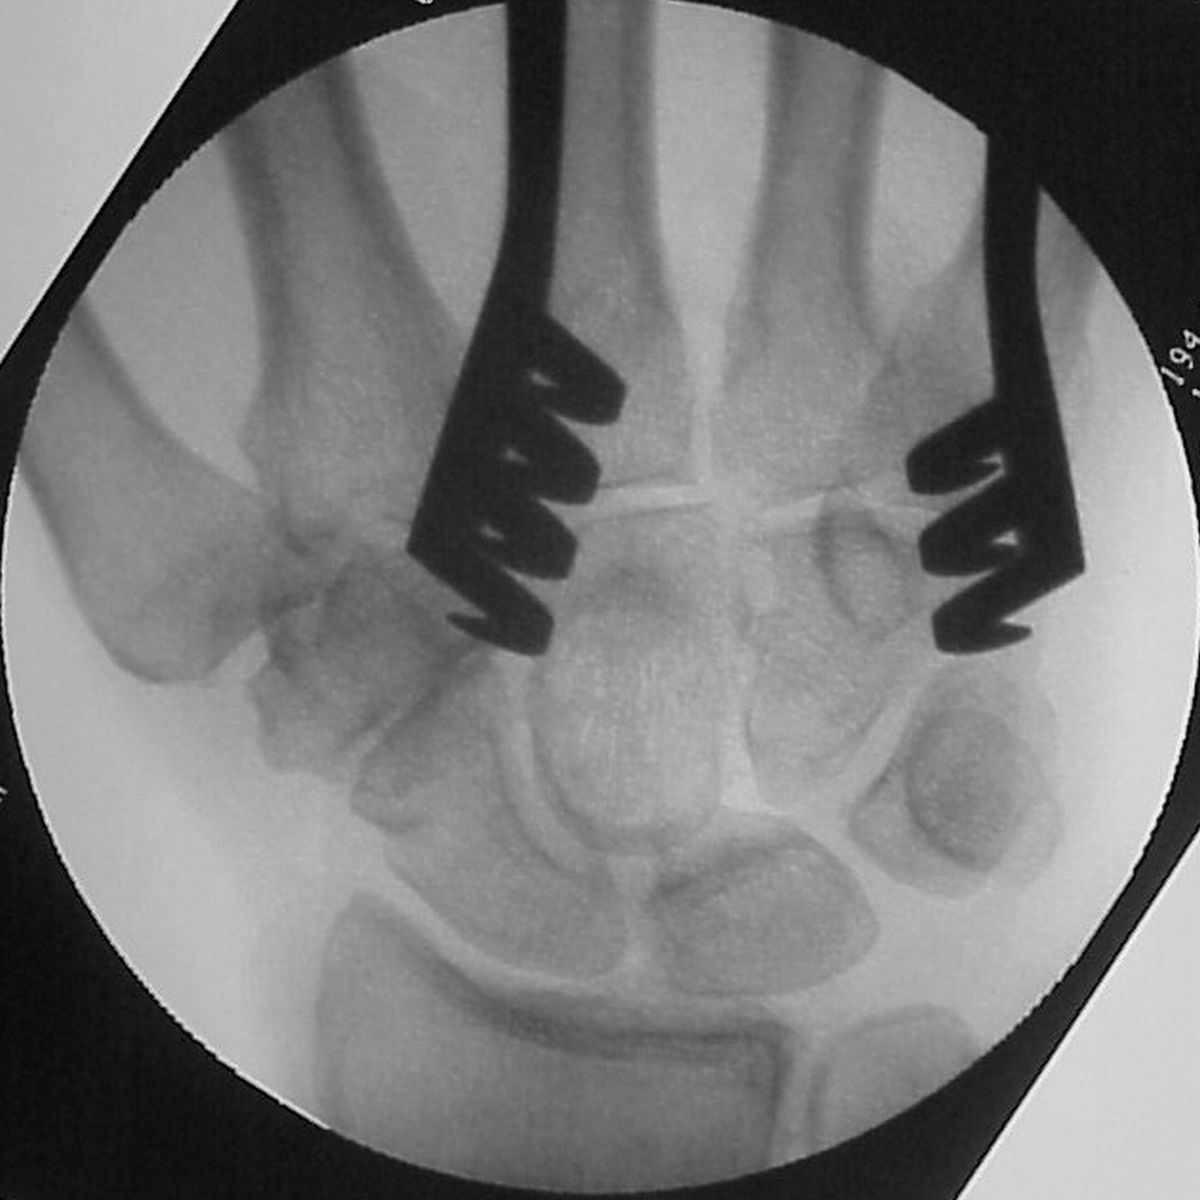

| Intraoperative

fluoroscopy of the defect after marginal excision with

a burr... |

| and then after the

defect was filled with corticocancellous iliac crest

bone graft to improve structural stability: |